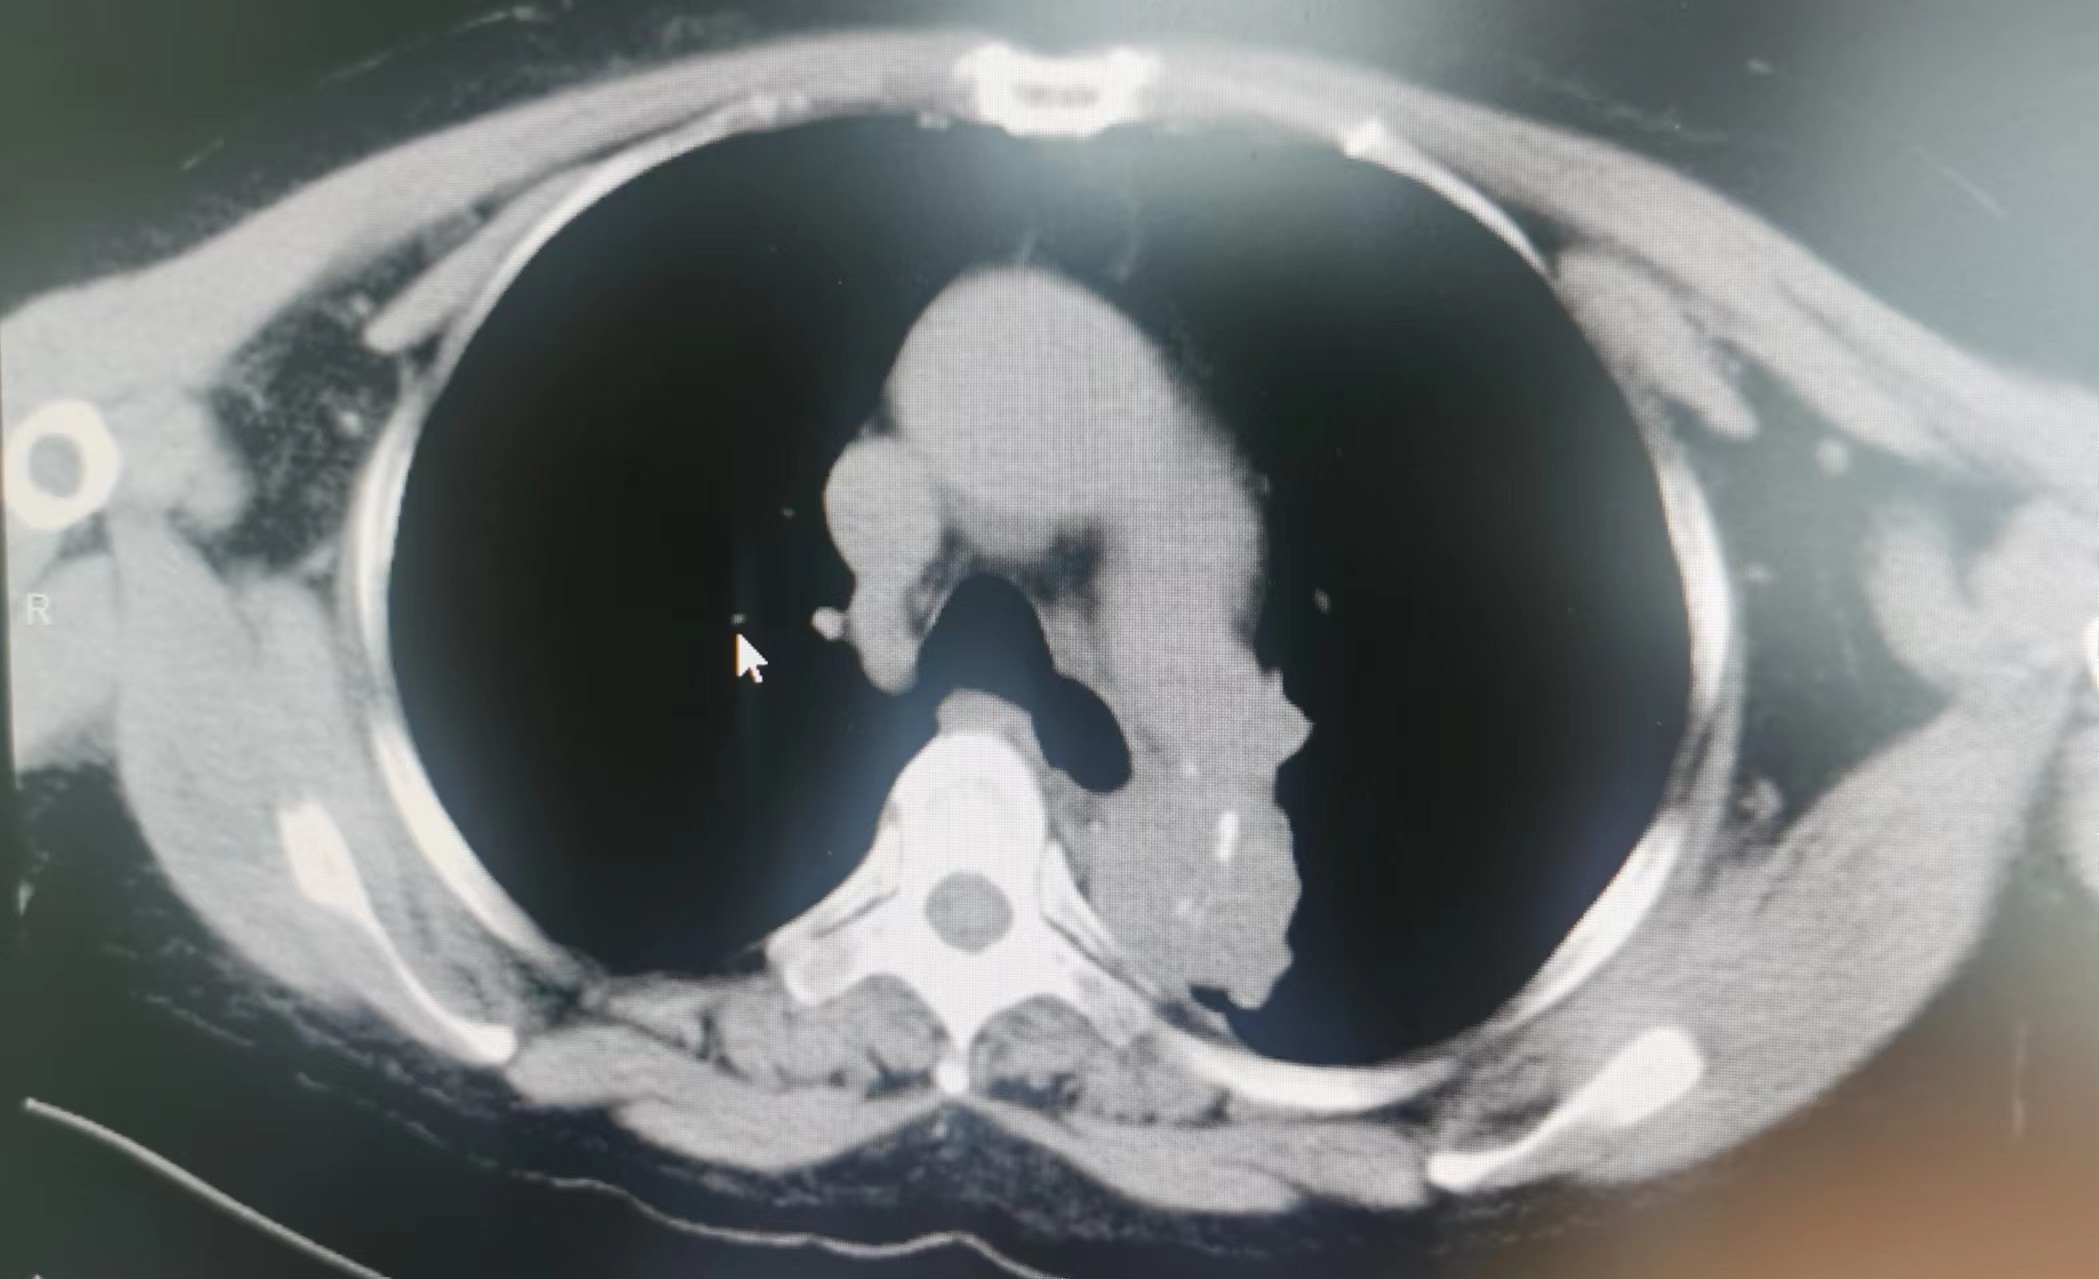

2023年11月,廖阿姨开始出现上腹部不适及胸痛,在外地医院住院治疗,当时查胸部CT考虑为:1.肺纤维化;2.双肺小结节;并经完善其他相关检查后考虑腹痛为:慢性胃炎(未行胃镜检查)。因临近过年,廖阿姨决定回本地过春节,在外地住院治疗10余日后和我院血液净化中心联系透析事宜。2023年12月,廖阿姨在我院透析时仍诉有上腹痛,值班医生经过仔细查体,感觉廖阿姨不像单纯慢性胃炎那么简单。首先,廖阿姨剑突下压痛不明显;其次,廖阿姨腹痛呈阵发性加重,加重时疼痛可累及左侧胸部,严重时胸部疼痛呈撕裂感,这些不像仅有慢性胃炎的症状。我院肾内科主任、主任医师李友河会诊后建议患者住院进一步检查,廖阿姨当日办理了住院。廖阿姨住院期间,肾内科予以相关治疗后其腹痛逐渐缓解,但未完全消失,经李友河主任、主管医生反复沟通和讲解病情后,廖阿姨及其家属终于认识到病情发展的严重性,从原本不愿检查的态度转变为同意完善胸部CT检查。经胸部CT平扫,结果为:1.主动脉夹层可能,建议进一步增强检查;2.右肺、左肺上叶少量慢性炎症;3.主动脉、冠状动脉硬化;4.心包少量积液,左侧胸腔少量积液。

当结果出来后,李友河主任第一时间查看了结果,并马上和患者家属沟通,建议廖阿姨马上行胸部CT增强扫描,同时,我院将立即开通绿色通道,转入我院深度帮扶医院——广东省人民医院进行救治。当晚,廖阿姨胸部CT增强结果提示为主动脉夹层,我院立即派出救护车和医护人员,全程护送廖阿姨至广东省人民医院进一步救治。廖阿姨先后在省人民医院心脏急危重症监护室、心内五科治疗,3日后,省人民医院专家为其行胸主动脉覆膜支架腔内隔绝术+暂时性经静脉起搏器系统的置入等治疗,2024年1月廖阿姨好转出院,并继续预约到本院透析。廖阿姨及家属在省人民医院出院后,十分感激我院及省人民医院的救命之恩,他们认为在省人民深度帮扶我院以来,佛冈县人民医院打出了“省医就在家门口的口号”,不管是佛冈县人民医院的医疗技术,还是医德医风均取得了很大的进步。随后,廖阿姨特地送来了锦旗,感谢全体肾内科医护人员的救命之恩。我院肾内科坚持“以患者为中心”的理念,进一步改善医疗服务,满足患者日常就医需求,为患者提供全周期的诊疗服务,在不断提高诊疗水平的同时,丰富服务内涵建设,改善患者就医体验,为广大群众生命健康保驾护航。科室简介